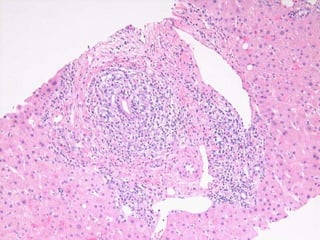

BS09-22346 49 yo, female.  Clinical history:  Acute hepatitis.  Mild elevation of IgG, ANA.  Viral serologies negative.  No drug/toxin exposure history.  AIH?

BS09-10453:  Dx: Chronic hepatitis, with severe activity (perivenular confluent necrosis) and focal fibrous septa, compatible with autoimmune hepatitis. Corresponds to: Modified Ishak stage 2/4 Metavir F2